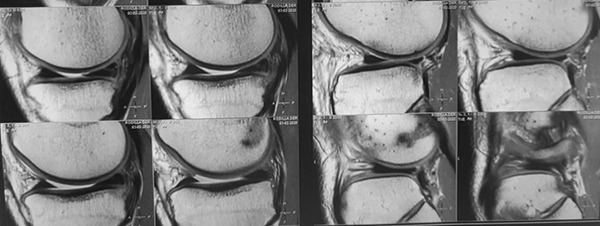

A continuación, se solicitó RM, donde se observaron, como datos positivos, la solución de continuidad completa de fibras del neoLCA de injerto autólogo de ST-RI de la revisión, lesión en tercio posterior de menisco medial, lesión en inserción posterior de menisco lateral y disrupción ligamentaria-capsular en sector anterolateral de rodilla con edema de partes blandas (figs. 2 y 3).

Figura 2: RM corte sagital. Lesión completa de plástica de revisión del LCA, presencia de tornillo tibial.

Figura 3: RM. Corte sagital. Lesión de ambos meniscos en su tercio posterior, traslación anterior de la tibia más evidente en el compartimento lateral.